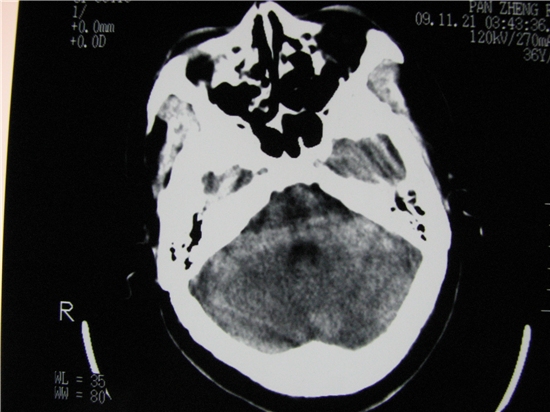

标题: CT23231:男 32岁 车祸伤,鼻腔内出血明显。 [打印本页]

标题: CT23231:男 32岁 车祸伤,鼻腔内出血明显。

额窦里是什么,骨窗怎么不清晰,是不窗宽窗位的事。

额窦内及额部软组织内可见多发游离类骨质密度影,考虑额骨骨折可能。

额窦致密骨瘤,前额部及右顶部头皮损伤伴异物存留

左侧额骨、鼻骨骨折,头面部软组织肿胀。

左侧额骨、鼻骨骨折,额窦内的应该是游离骨块